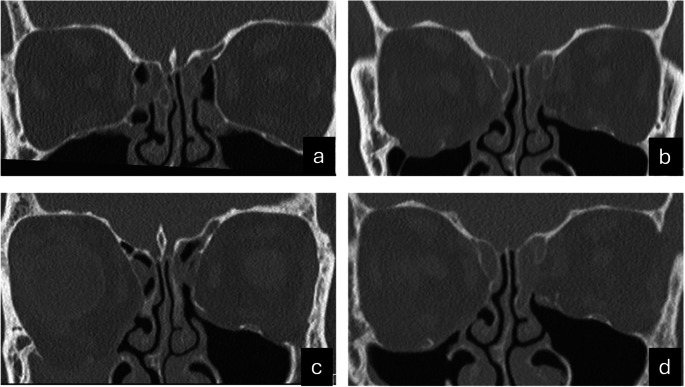

Objectives: Silent sinus syndrome (SSS) is a rare condition characterized by progressive maxillary sinus collapse, causing enophthalmos and hypoglobus without sinusitis symptoms. Secondary SSS arises from trauma or surgery disrupting mucociliary clearance. This study aims to analyze CT scan features, evaluate the timeline of SSS development, and identify contributing factors.

Materials and methods: Patients diagnosed with secondary (post-traumatic or iatrogenic) SSS between January 2015 and January 2024 at the Erasmus Medical Center were reviewed. Characteristics from pre-SSS (T1) and post-SSS (T2) stages, management, and clinical outcomes were recorded. Data on patient demographics, symptoms, orthoptic findings, and the time interval between trauma or surgery and SSS onset were also collected.

Results: Nine patients (six males and three females) met the inclusion criteria. The time from trauma or surgery to SSS onset ranged from one to thirty-six months, with a median of three months in the posttraumatic group. All patients presented with unilateral enophthalmos or hypoglobus; eight reported diplopia. Surgical management, including retrograde uncinectomy and orbital reconstruction, restored orbital anatomy and resolved symptoms.